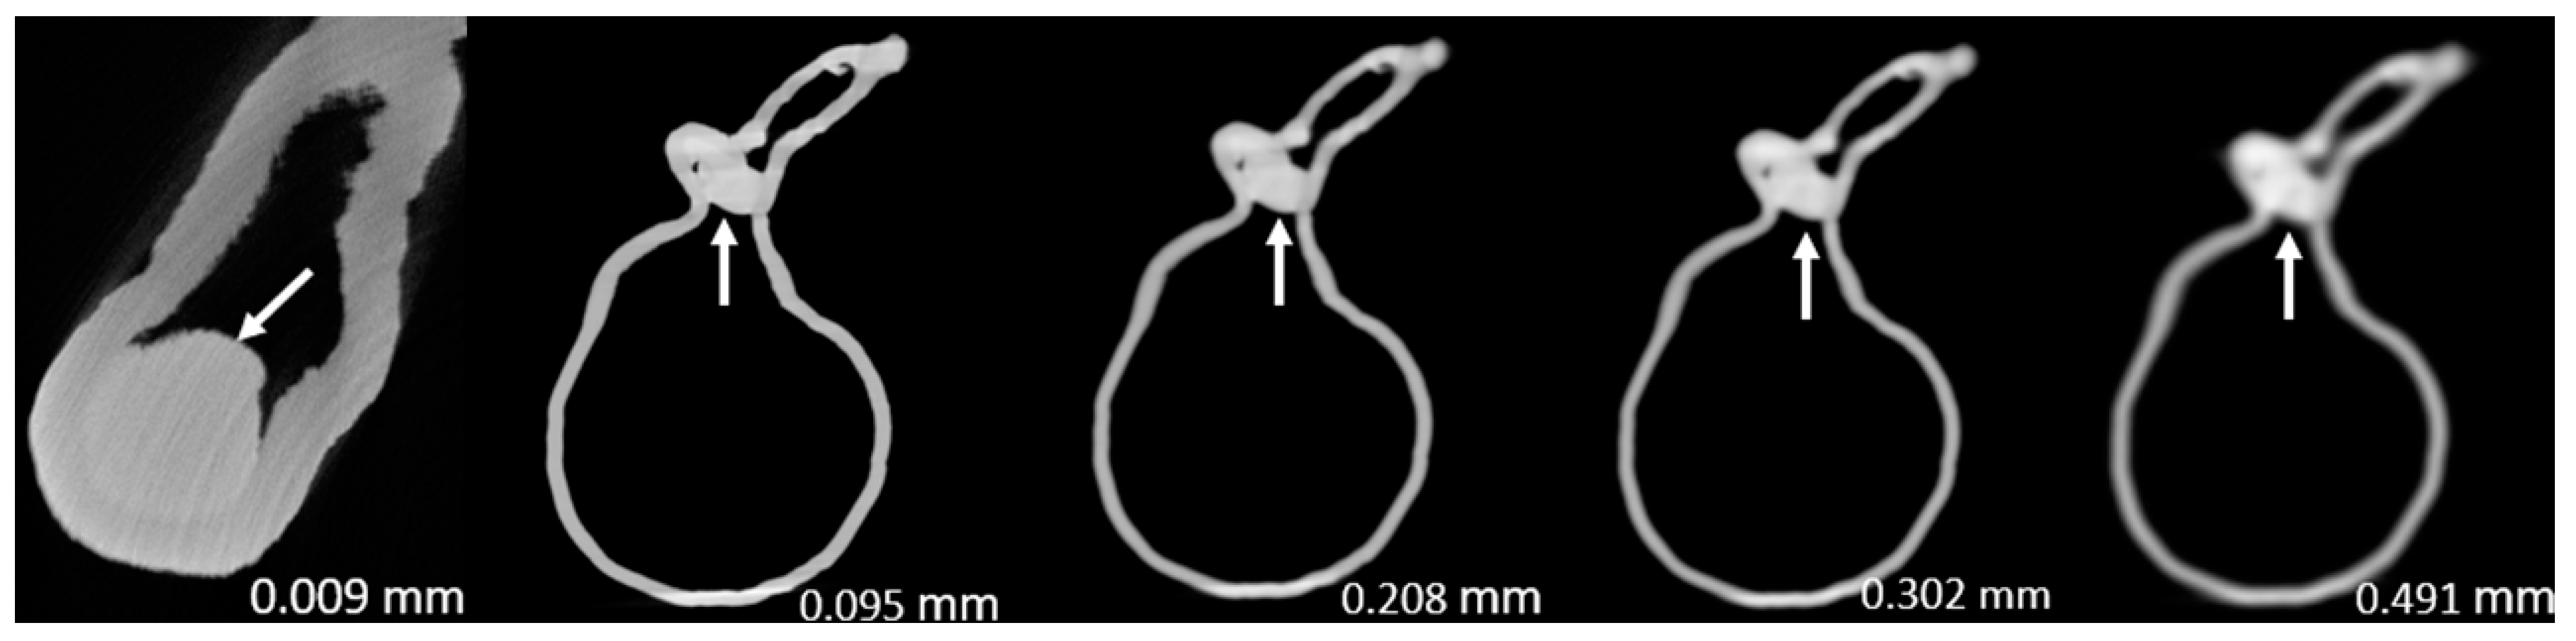

Figure 3, Figure 4, Figure 5, Figure 6, Figure 7 and Figure 8 show the micro-CT and SRCT images of plaques 1 and 2 in models 1-3 that were used for the stenosis assessments. For the micro-CT (0.009 mm slice thickness) images, only the stenotic areas were illustrated due to the processing power limit of the workstation for handling data with a very large matrix (7872×7872). The micro-CT (0.009 mm slice thickness) images were able to clearly demonstrate patent areas between the calcification and the left coronary arterial walls, especially in severe stenosis compared with SRCT (0.095-0.491 mm slice thickness) images (Figure 3, Figure 4 and Figure 5 with >90% stenosis).

Figure 4. Two-dimensional micro-computed tomography (micro-CT) (0.009 mm slice thickness) and synchrotron radiation CT (0.095-0.491 mm slice thickness) images of plaque 1 in model 2 causing >90% stenosis (reprint of synchrotron radiation CT images with permission [15]).